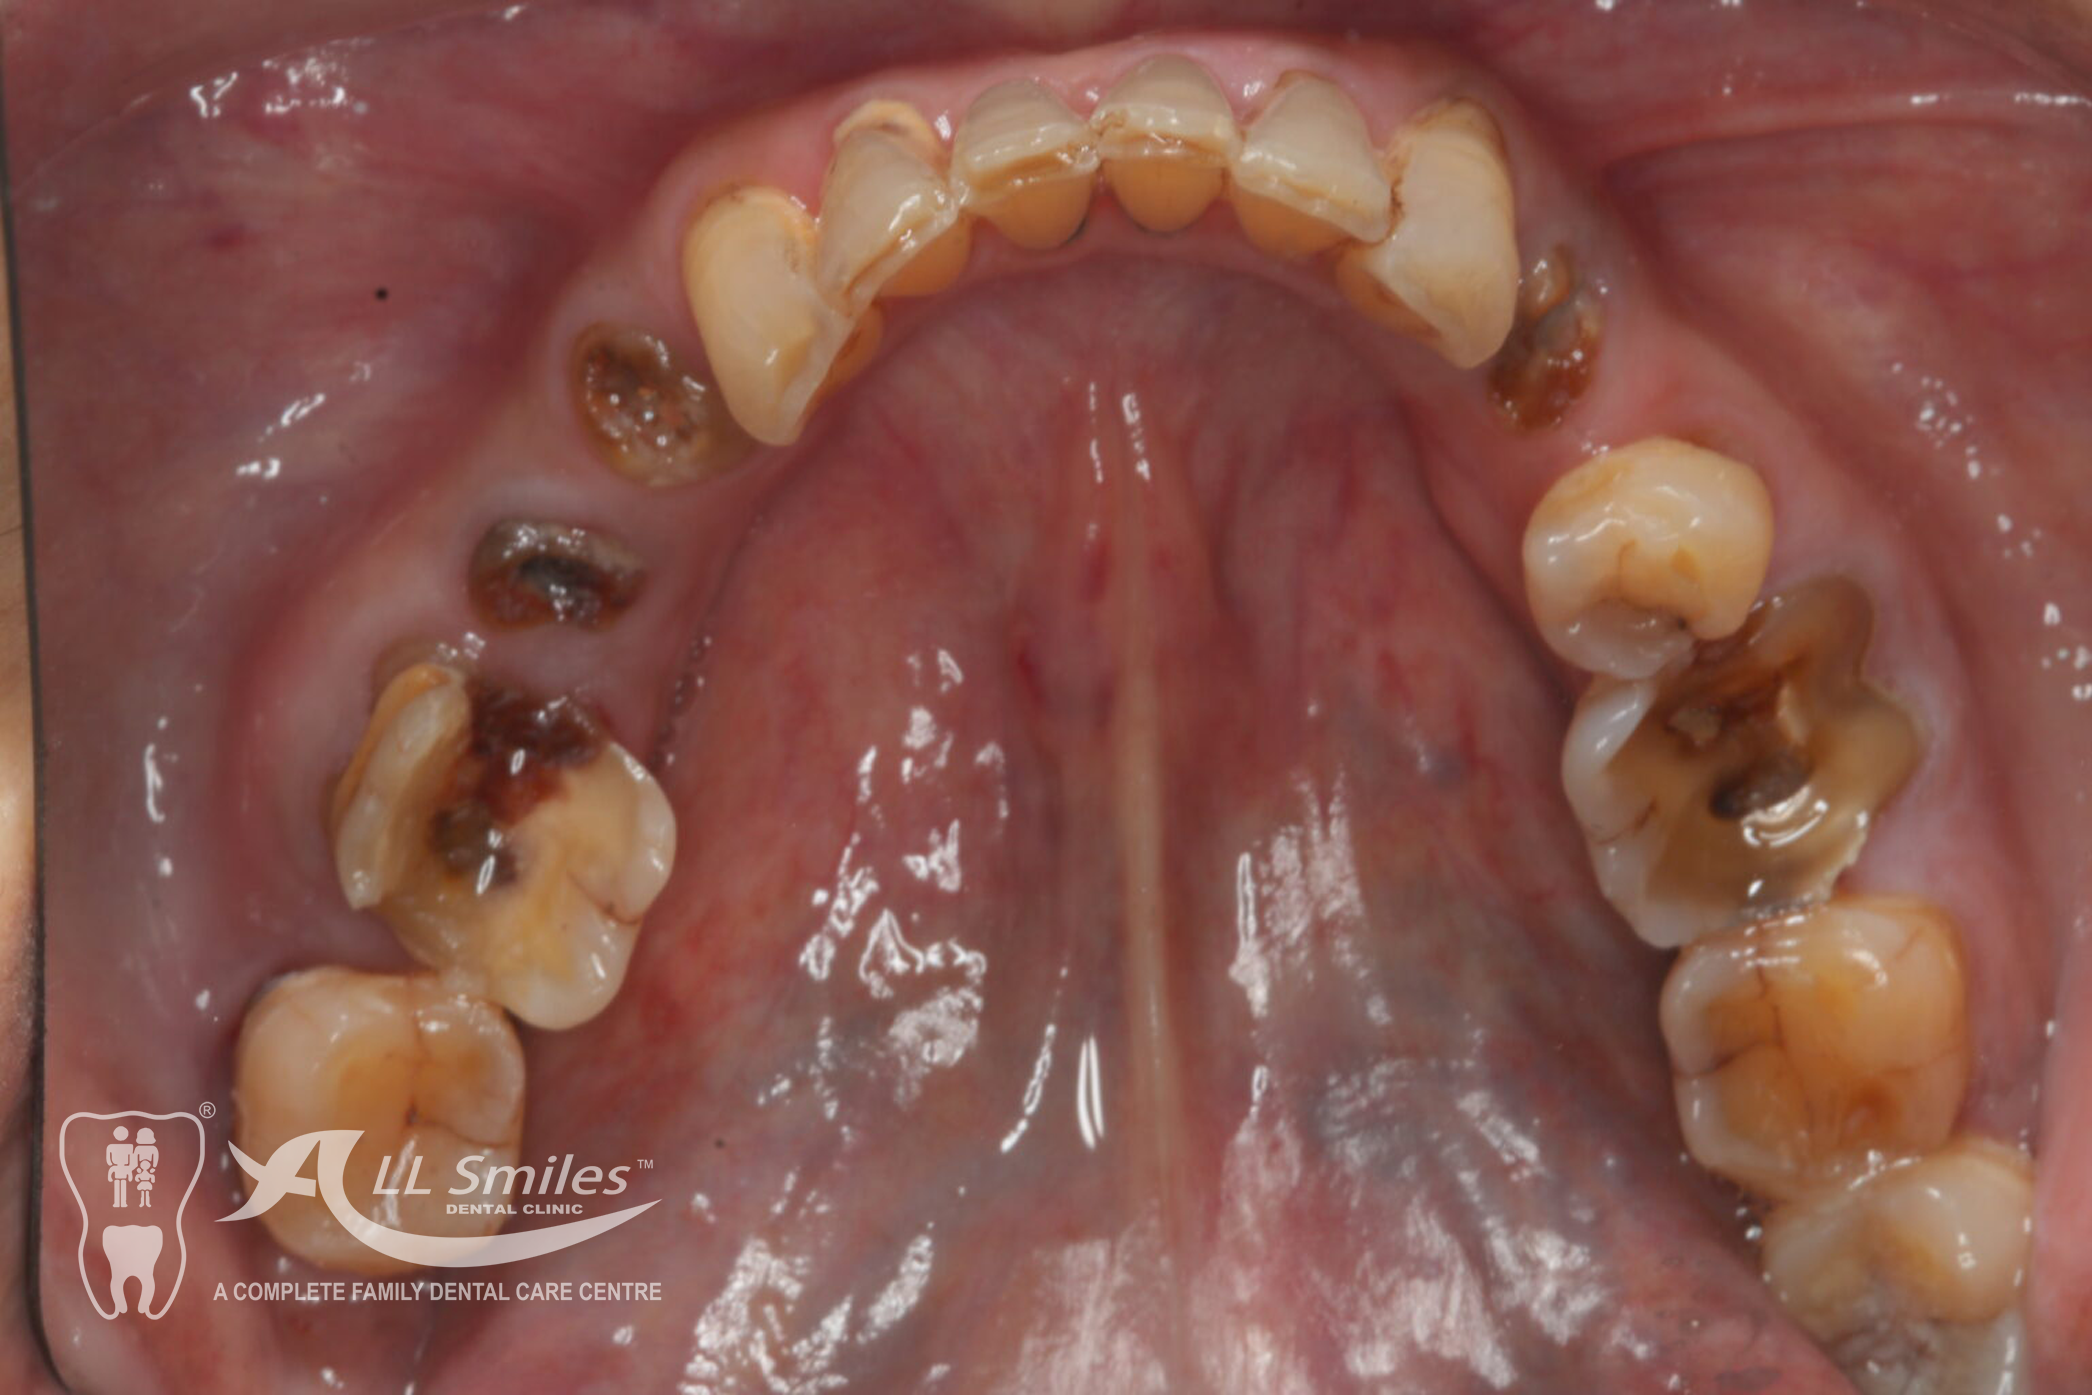

Crowns & Bridges Gallery